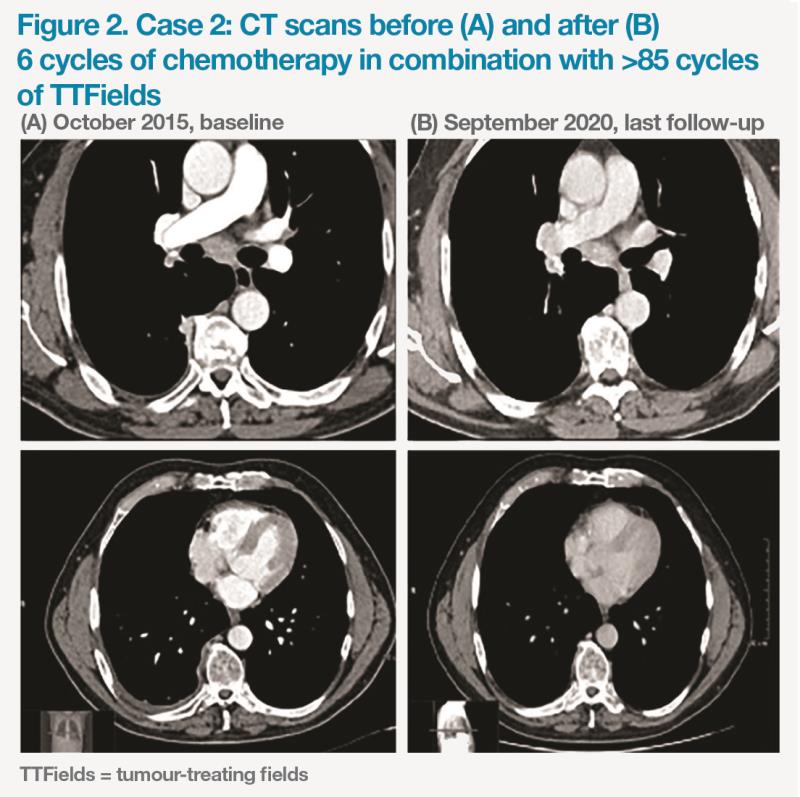

A 63-year-old male patient with biphasic MPM was commenced on six cycles of TTFields plus carboplatin/pemetrexed in October 2015, followed by TTFields maintenance. He experienced mild, chemotherapy-related hepatotoxicity, mucositis and a hypersensitivity reaction to carboplatin (all grade 1), with no skin toxicity reported, in spite of high compliance with TTFields (median ≥18 hours/day) The patient had a PR (near-complete response), with no disease progression for >60 months as of November 2020. (Figure 2) Currently, the patient is in good clinical condition and remains on maintenance therapy with TTFields.